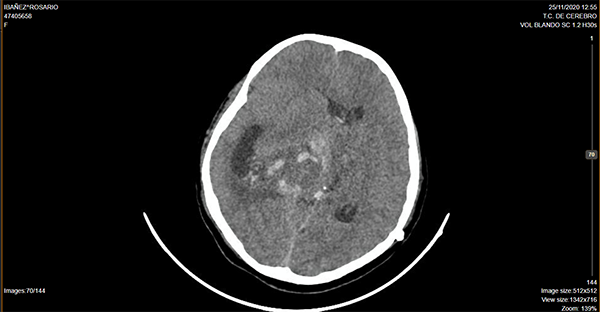

Caso ilustrativo n°2: Houkin tipo 2(Figura 2)

Paciente de 14 años de edad, consultó por deterioro del sensorio, cefalea y vómitos, se realizó tomografía computada de cerebro donde se evidenció lesión ocupante de espacio supratentorial intraventricular. Se programó cirugía, se realizó exéresis parcial. Cursa postoperatorio intubada en terapia intensiva presentado descompensación hemodinámica a las 24 hs, imagen por tomografía computada de cerebro que evidencia sangrado intratumoral, se reexplora la lesión, paciente evoluciona desfavorablemente.

Se consideró Houkin tipo 2, ya que el evento adverso estuvo relacionado con el procedimiento quirúrgico pero no era ni esperable ni evitable.

Figura 2: Imagen por Tomografía Cerebral computada donde se observa lesión ocupante de espacio intraventricular centroencefálica, con sangrado intratumoral y desvío de línea media.